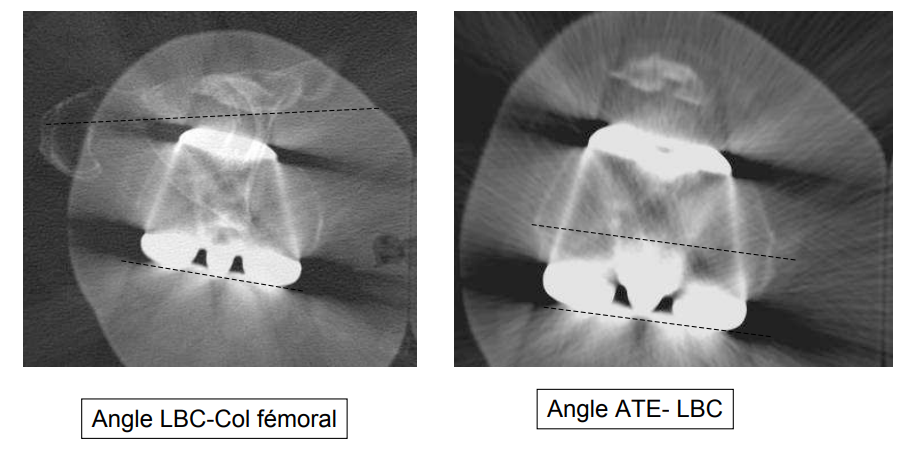

Evaluation de la pièce fémorale

- Axe LBC-col fémoral

- Angle LBC-ATE

LBC = Ligne Bi-Condylienne ATE = Axe Trans-Epicondylien